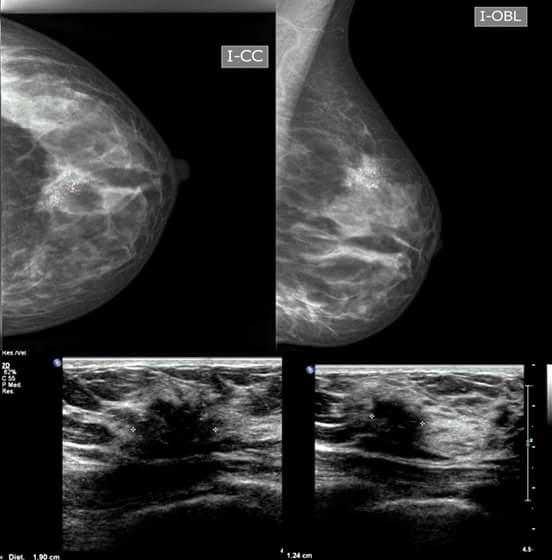

ECOGRAFÍA DE MAMA